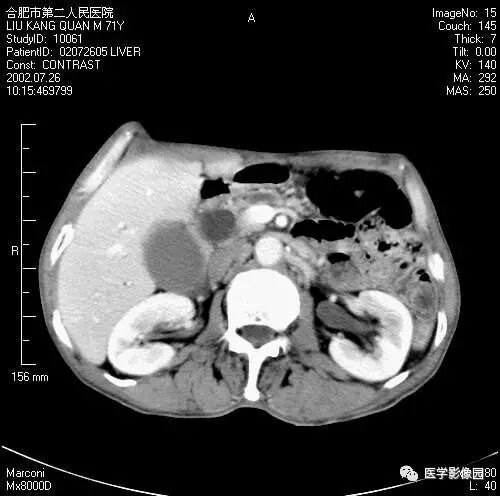

图6-4-14胰腺癌

A.CT平扫见胰体、尾部分叶状肿块,

其内见境界不清的低密度区;

B.增强扫描肿块内低密度更加清晰